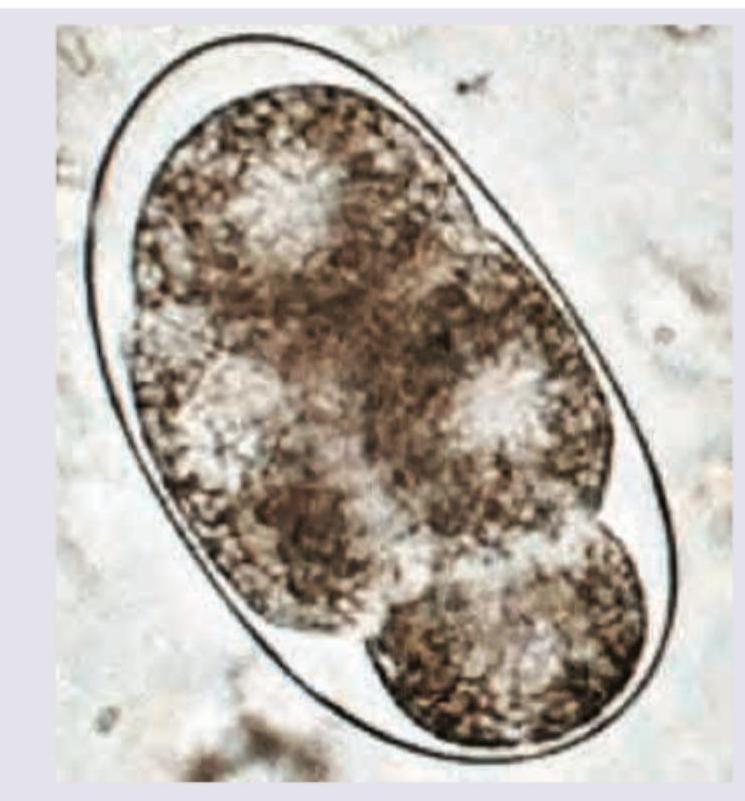

Question 8: The image shown below shows egg of? (AIIMS May 2017)

- C. A. lumbricoides (Correct Answer)

Explanation: ***A. lumbricoides*** - The image displays a **mammillated outer layer** and an **oval shape**, characteristic features of a fertilized *Ascaris lumbricoides* egg. - The internal content shows a **developing embryo** (morula stage), which is typical for newly passed *Ascaris* eggs. *A. duodenale* - The eggs of *Ancylostoma duodenale* (hookworm) are typically **oval or ellipsoidal**, have a **thin, transparent shell**, and contain a **segmented ovum** (usually 2-8 cells) when passed in stool. - They lack the distinctive **thick, mammillated outer layer** seen in the image. *E. vermicularis* - *Enterobius vermicularis* (pinworm) eggs are **D-shaped** or **asymmetrically ovoid**, with one side flattened. - They possess a **thin, smooth shell** and contain a **larva**, which distinguishes them from the egg shown. *Strongyloides stercoralis* - *Strongyloides stercoralis* eggs are rarely seen in stool samples because they usually **hatch within the intestine**, releasing **rhabditiform larvae**. - When present, they are **oval, thin-shelled**, and contain a **partially developed larva**.